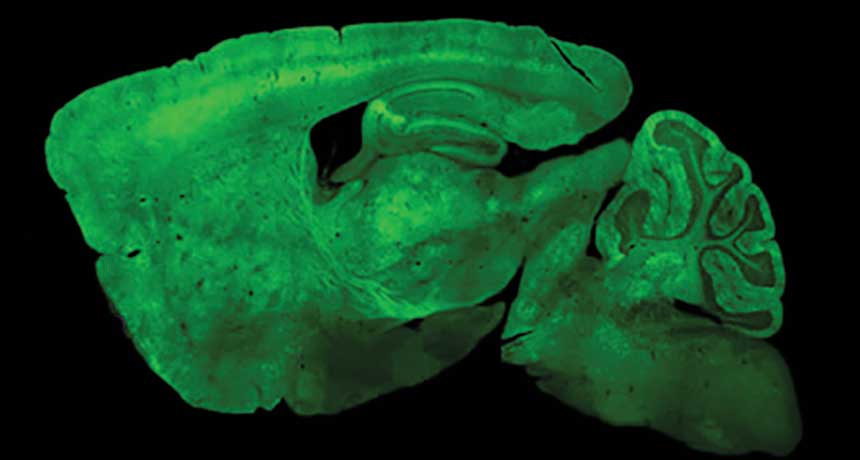

Brain cells aglow after viral delivery

PACKAGE DELIVERED The whitish dots in this micrograph are neurons called Purkinje cells in the cerebellum of a mouse. Their color is due to a gene the cells received from the virus AAV-PHP.B.

B. Deverman and the Gradinaru laboratory/Caltech